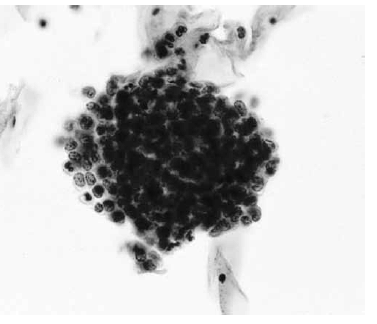

Nas questões de números 46 a 60, assinale a alternativa que melhor corresponde ao diagnóstico do quadro microscópico apresentado.